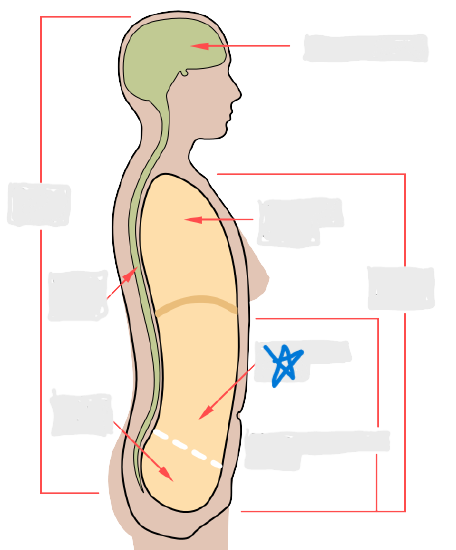

axial

cephalic

occipital

frontal

otic

orbital

nasal

oral

mental

cervical

dorsal

scapular

vertebral

lumbar

sacral

gluteal

thoracic

sternal

mammary

axillary

abdominal

umbilical

pelvic

inguinal

pubic

perineal

appendicular

acromial

brachial

antecubital

olecranal

antebrachial

carpal

manus

coxal

femoral

patellar

popliteal

crural

sural

peroneal

calcaneal

plantar

dorsal/posterior

ventral/anterior

lateral

medial

distal

proximal

superficial

deep

superior

inferior